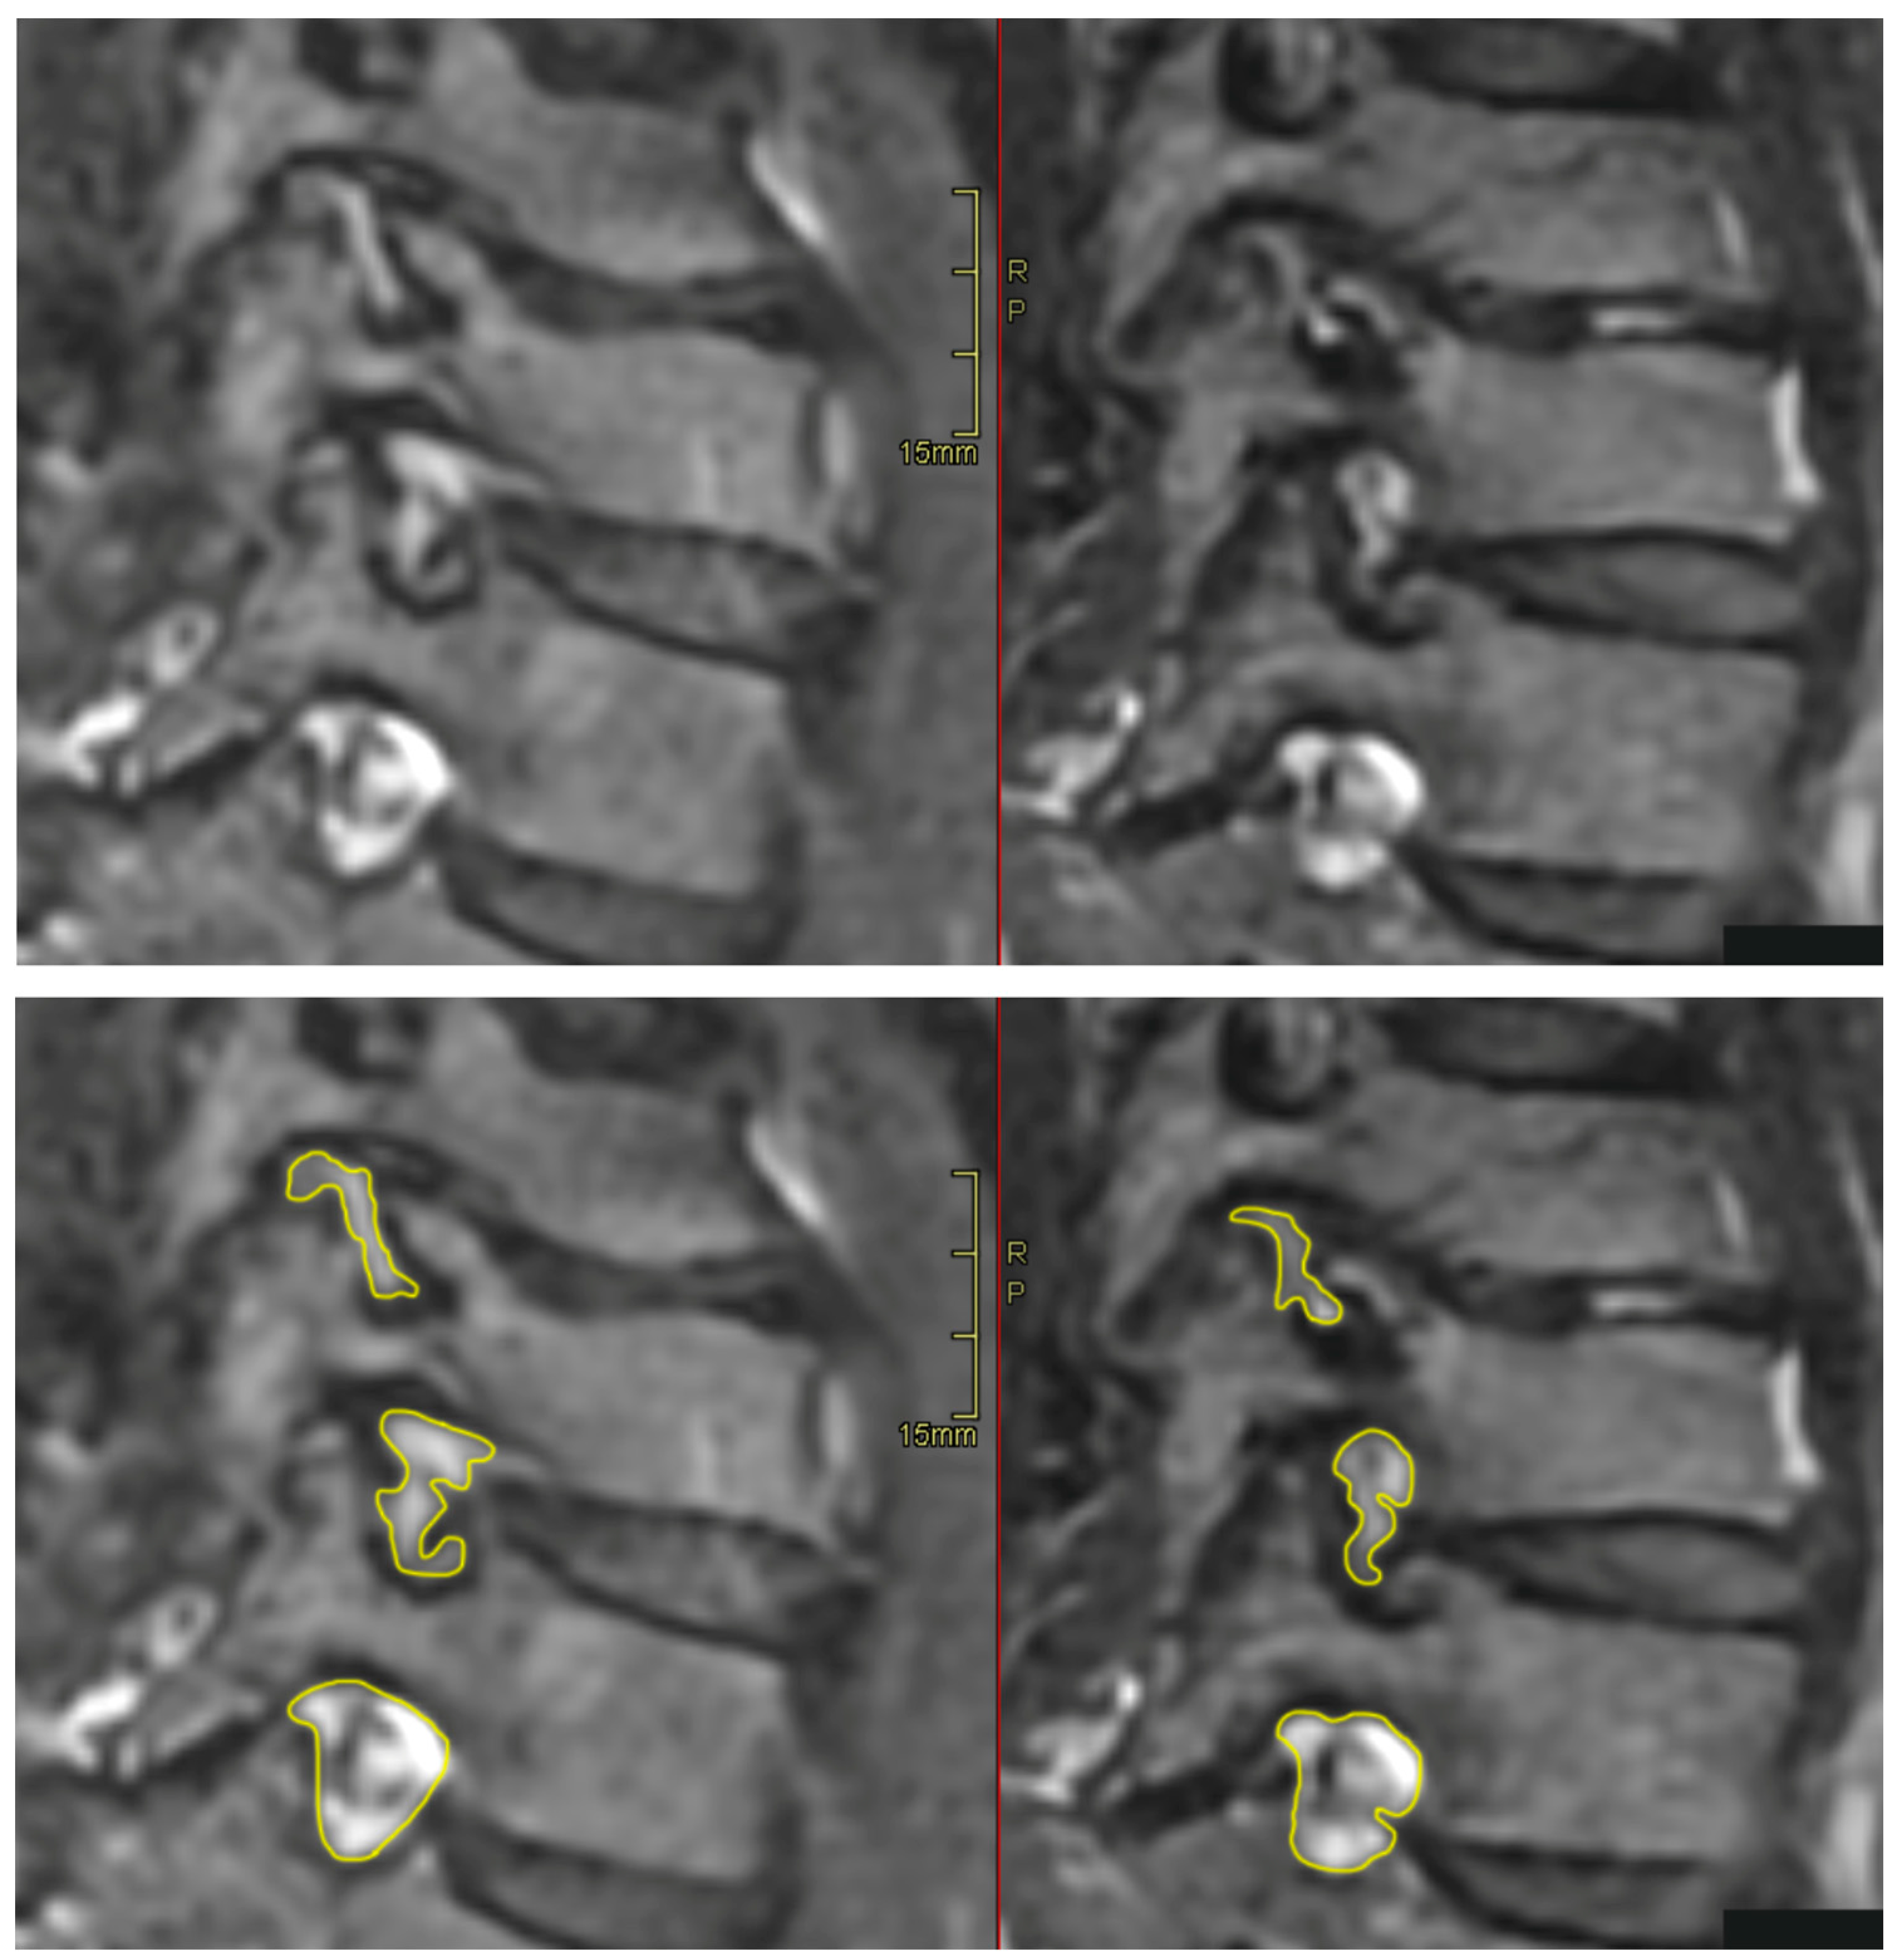

All patients were positioned without any complaints in the DMRICS apparatus, outside the MRI gantry. The patients were subsequently positioned within the MRI for a relaxed image acquisition. After successfully conducting the simulated Spurling test, immediate imaging was performed, which produced clinically acceptable image quality in 9 out of 10 patients in both relaxed and provoked position, as shown in Figure 2.

Significant changes of gradings of Park and Kim classifications respectively after provocation (both p = 0.000) were seen. After applying the simulated Spurling test, all initially labeled stenotic foramina were classified as Park grade 2 or 3, with some moving up by 1 grade and others by 2 grades. In 13 out of 27 gradings by Park and 9 out of 27 gradings by Kim escalated to a higher grade after provocation. However, there were no significant alterations in the quantitative assessments. In foramina with high Park gradings (2 or 3) in the relaxed images, only minor area changes were observed, depicting that the degenerative segments are less dynamic, see Figure 3.

The significant increase of the qualitative gradings of the foramina, when comparing MRI before and during the simulated Spurling test, indicate that a Spurling test leads to higher Park and Kim grades. This offers not only insights into the variations of the often-employed clinical Spurling test but also proposes a possible clinical utility for dynamic MRI. The method could help in determining the severity of foraminal stenosis and identifying the impacted nerve roots if they are not distinctly discernible in a routine, relaxed MRI. Especially when several foramina are narrow on a routine MRI and the symptoms and clinical examination can´t discriminate which nerve root(s) that are giving rise to the experienced pain. However, for the foraminal area and cross-distance measures no significant changes were detected in the present work. The reason for these contradictory findings may be that the foraminal shape shifts with compression and thereby the nerve compression may increase even if the overall area is not changed or even increases, see Figure 2. Further, the magnitude of measurement error in such small structures, especially for the axial-cross distance measurements may also play a role here.

Figure 2. The upper left depicting an oblique image in a relaxed position compared to the right image taken during the Spurling test. The foraminal areas are marked in the lower pair of images.